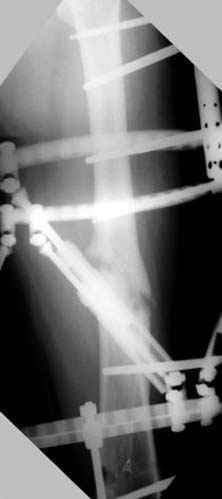

Несколько снимков из моей коллекции, чтобы разьяснить, почему мы до сих пор делаем различные варианты остеотомии.

На рисунке N1 предоперационный план лечения ложного сустава шейки бедра- линия ложного сустава, угол и направление введения импланта, клиновидная остеотомия в градусах и миллиметрах, второй снимок после коррекции, расчет, на сколько удлиняется конечность и размеры импланта;

N3 рисунок окончательный снимок, после операции моя рентгенограмма должен выглядеть примерно как эта картина. На N4 снимке клин перед удалением; N5 послеоперации 3 нед.; N6 окончательная рентгенограмма.

Отправитель: Djoldas Kuldjanov 23 Ноябрь 2004, 18:21

пластическая модель; и коррекция бедра аппаратом Илизарова.